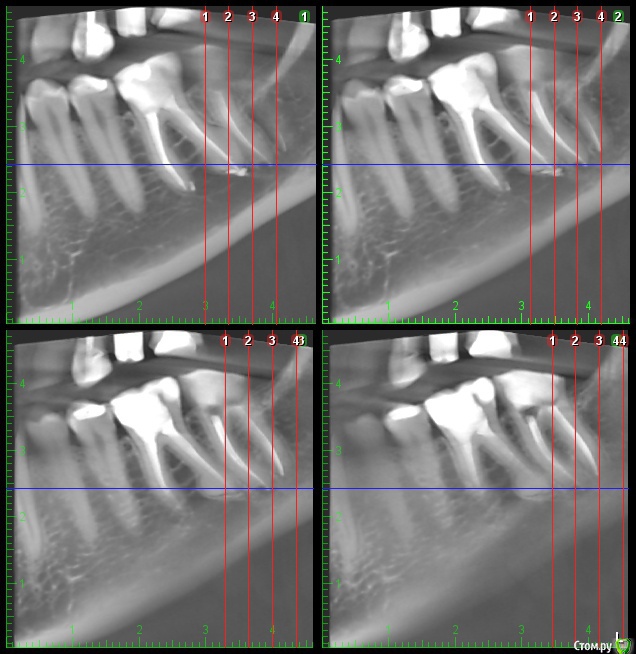

inSight Опубликовано 12 февраля, 2017 Поделиться Опубликовано 12 февраля, 2017 смотреть за динамикой. Неужели эту боль придумывает голова? У меня уже сил нету это терпеть. До лечения ведь вообще ничего не болело. Тянет-распирает-ноет-давит преимущественно снизу в районе 36 и 37 зуба. Но как его раскрывать, когда откуда-то идёт давяще-ноющее-распирающее ощущение? я затрудняюсь ответить, не нравится мне ваш 27 зуб смотрю кт и вот не пойму толь пропущенная анатомия. Нужна помощь более опытных. Ссылка на комментарий

inSight Опубликовано 14 февраля, 2017 Поделиться Опубликовано 14 февраля, 2017 Вродеб нормально. Апну тему. http://s011.radikal.ru/i315/1702/ce/2415863cdd83t.jpg http://s42.radikal.ru/i096/1702/76/855feb5eec66t.jpg http://s019.radikal.ru/i639/1702/15/7b20e47e5e0dt.jpg http://i062.radikal.ru/1702/b5/957a4094f4bet.jpg Ссылка на комментарий